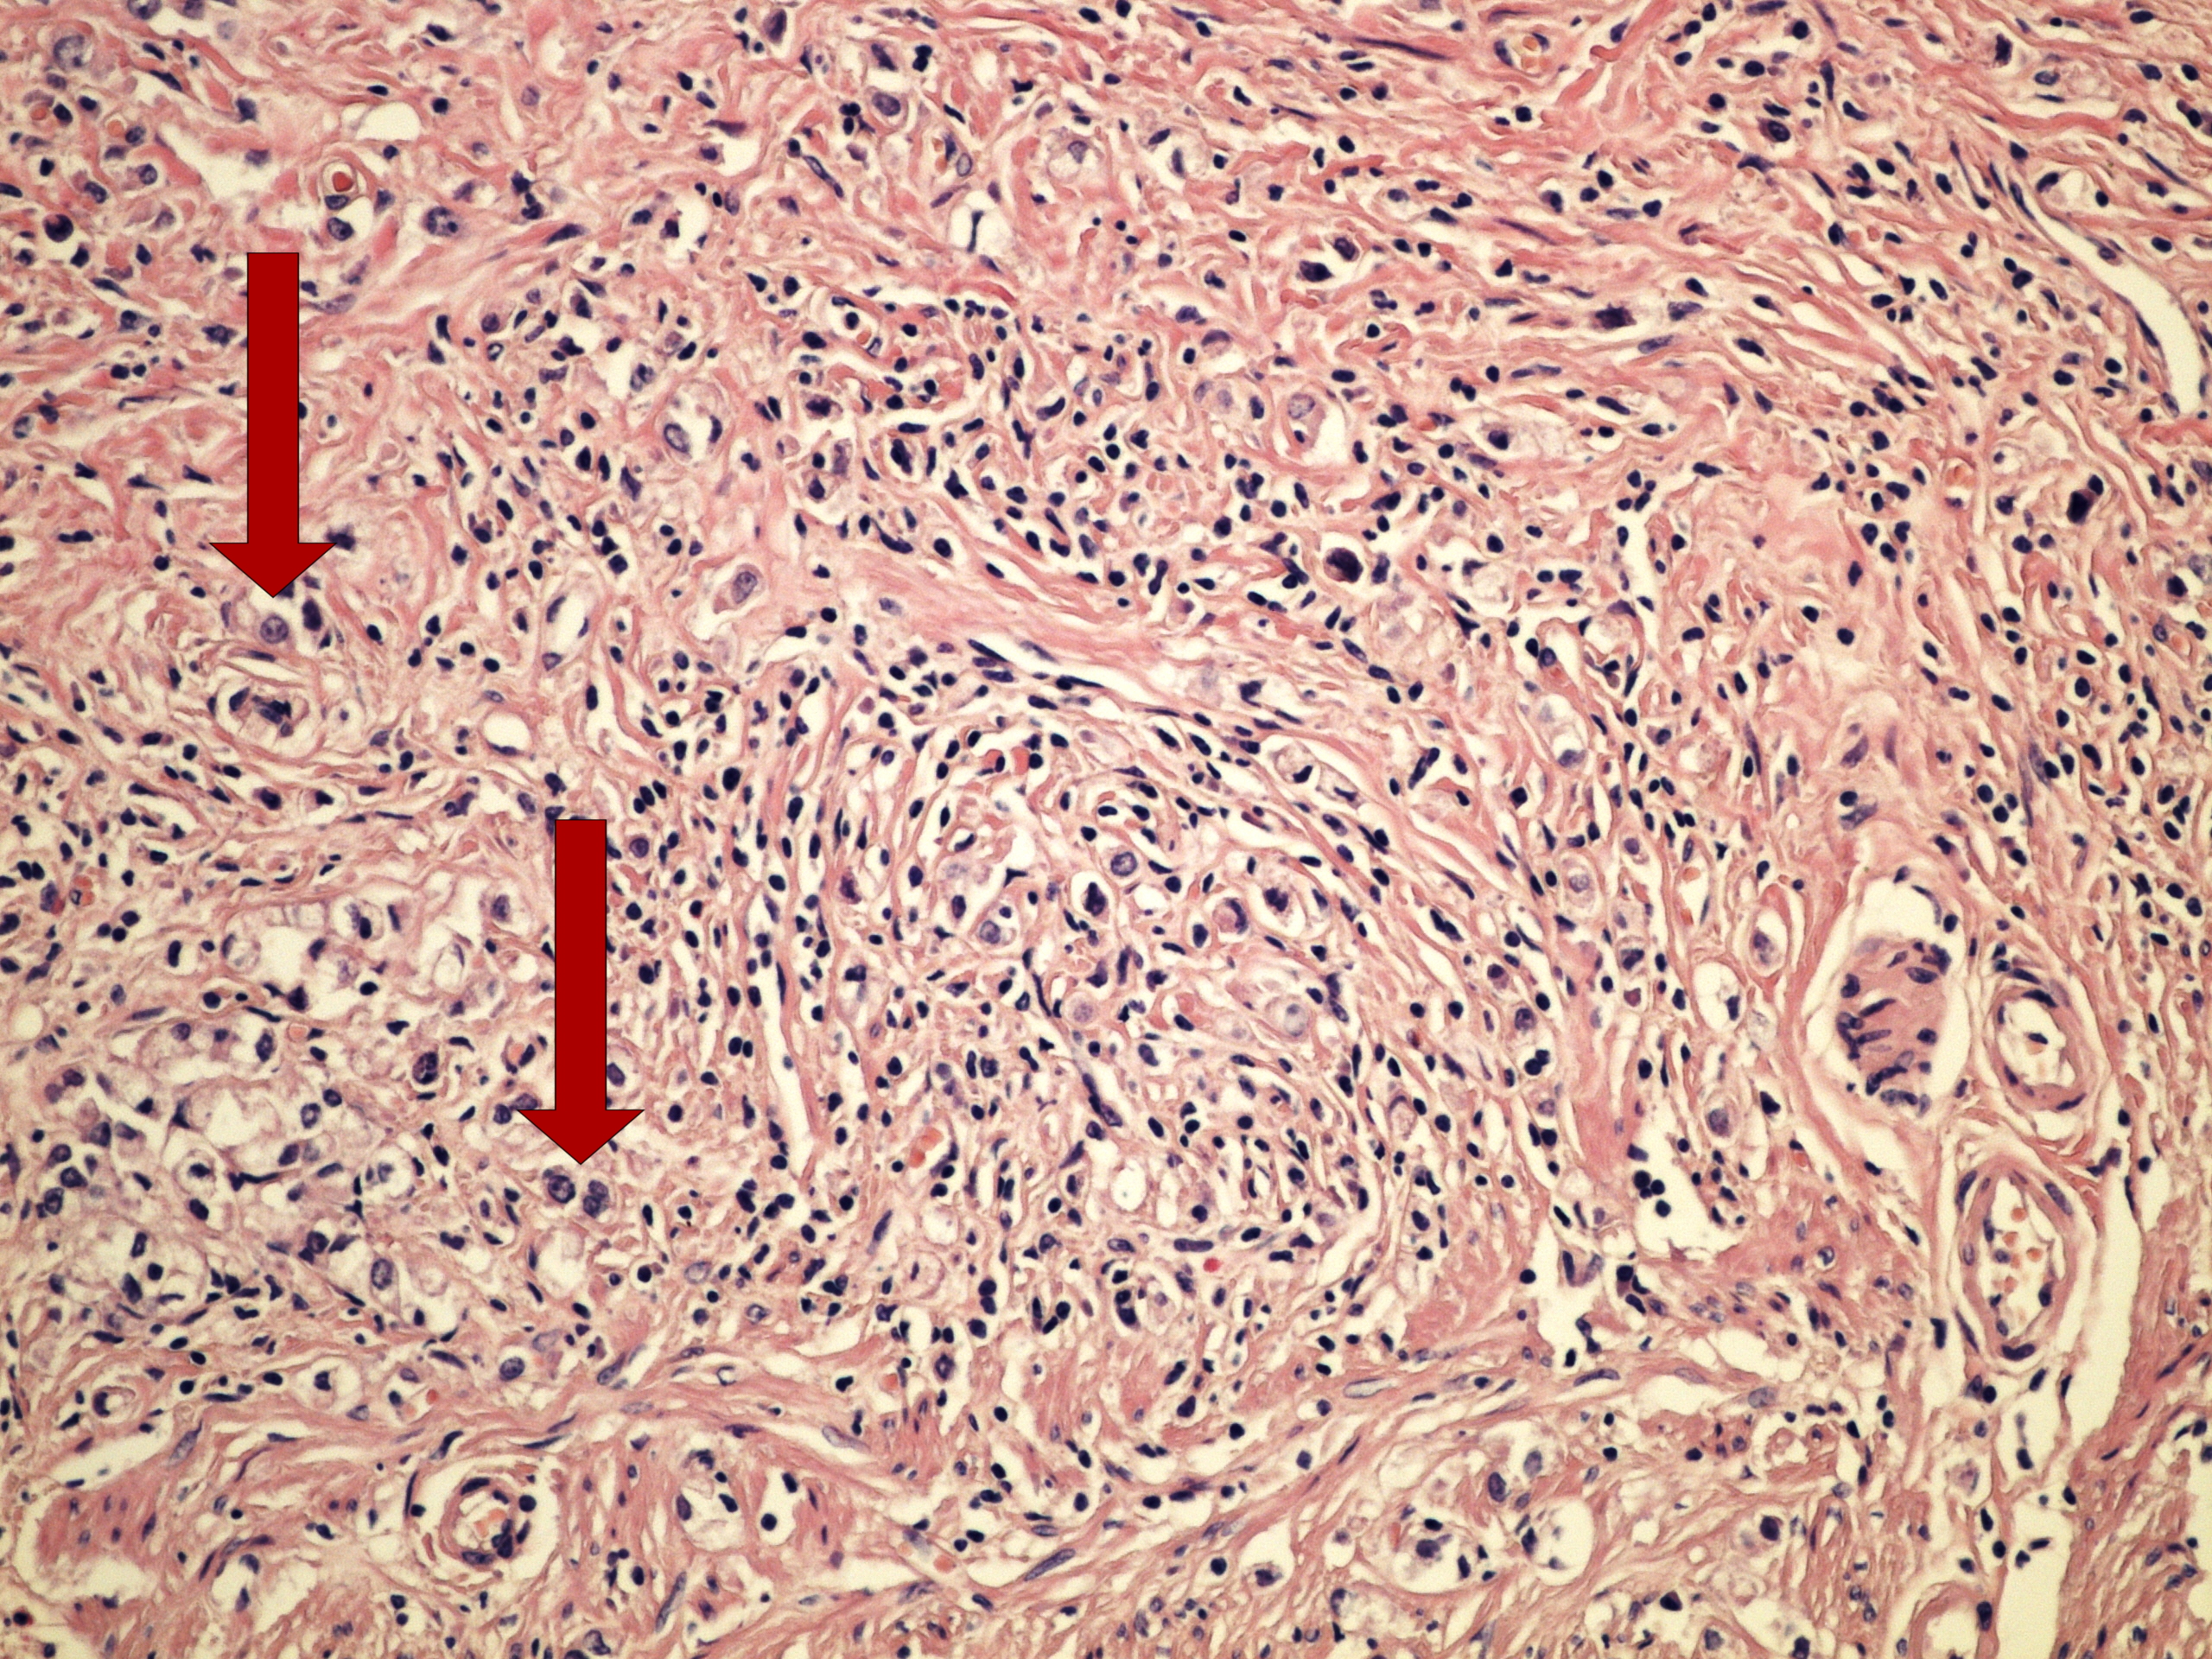

Preparát č.7 a č.8 - solidní adenokarcinom

Struktury

- stroma nádoru

- tumor

- nekróza